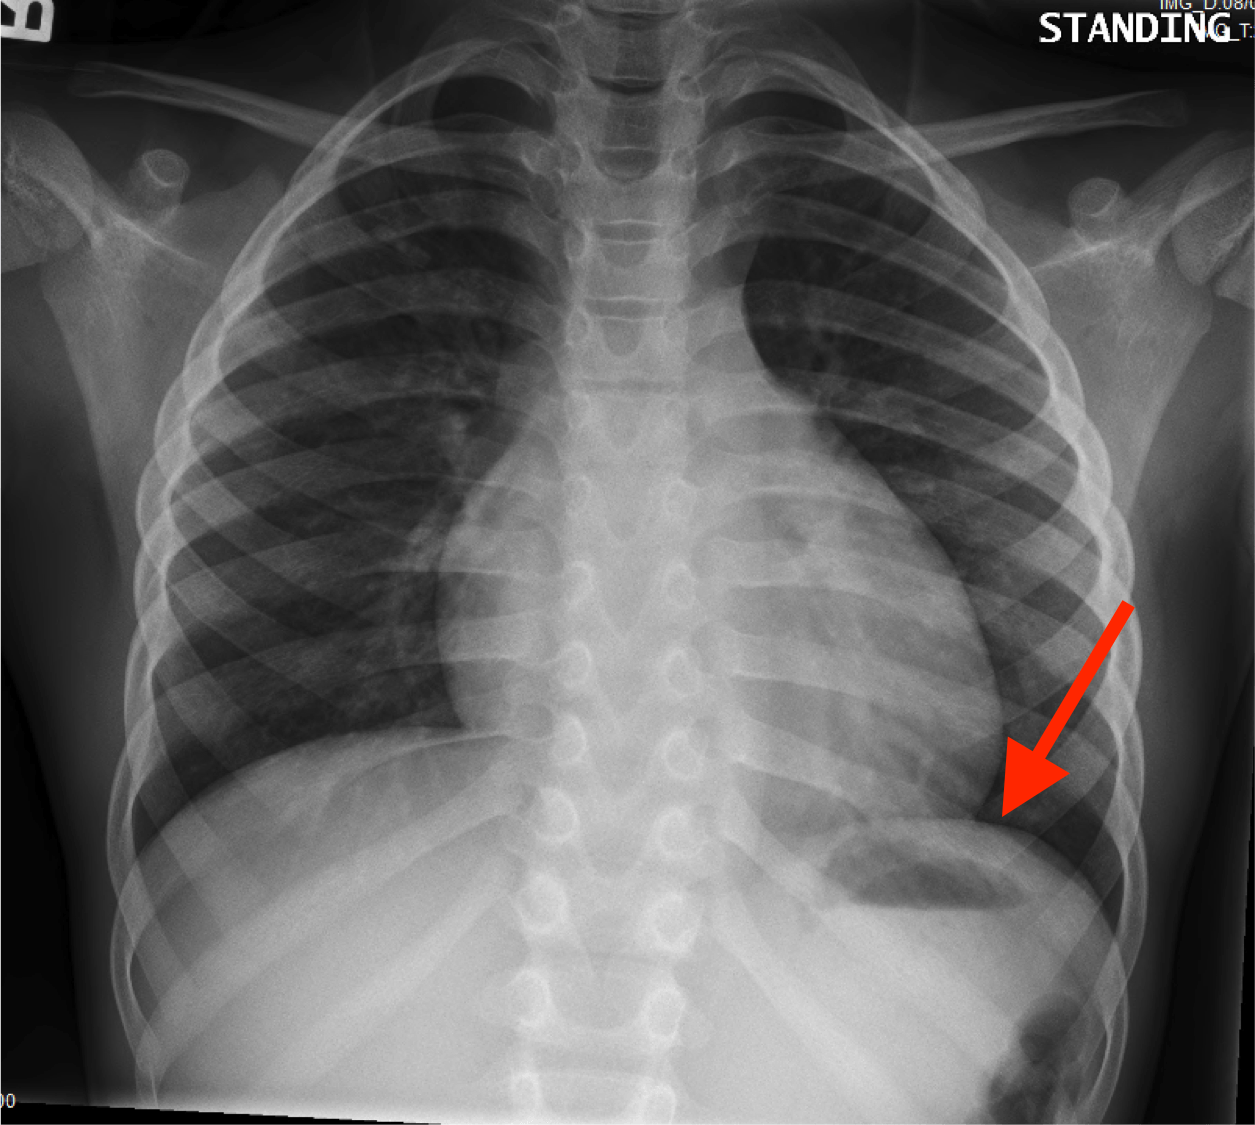

What is the red arrow indicating?

Is this a normal finding on a CXR?

A

• Gastric bubble

• This is a normal finding on a CXR

Free air: Instead of the air being contained inside the stomach to the unitlateral side of the diaphgram, air will be displaced bilaterally on both sides of the diaphragm.